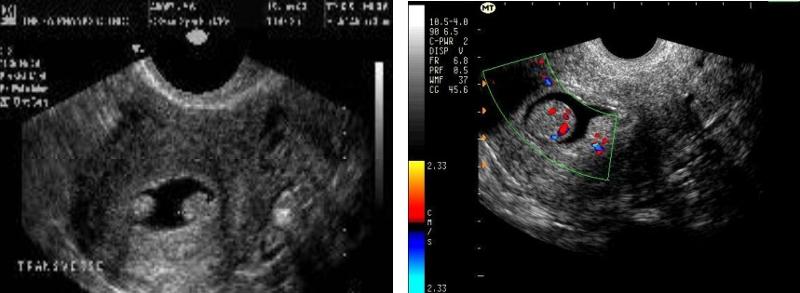

Sonohysterografía

Se introduce un catéter hasta la cavidad uterina (endometrial) y se inyecta normal salina.

El líquido expande las paredes de la cavidad y permite evaluar anomalías en el endometrio, pólipos y miomas sub-mucosos.

Poplipos por Sonohisterografía (imagen)

Hiperplasia Endometrial (imagen)